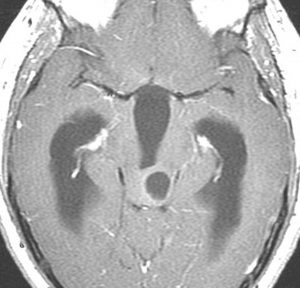

19歳で偶然見つかった例

頭部打撲で検査され偶然発見された19歳男性ものです。中脳視蓋全体が腫大して腫瘍化しています。左側にのう胞があり周囲が淡くガドリニウムで増強されます。

中脳水道の癒着閉塞により,高度の停止性水頭症になっています。高身長ですが頭囲が61cmありました。小さい頃から頭が大きいので家族も気にならないようです。数年以上あるいは10年近くの長期にわたってこの水頭症は変わらないのでしょう。